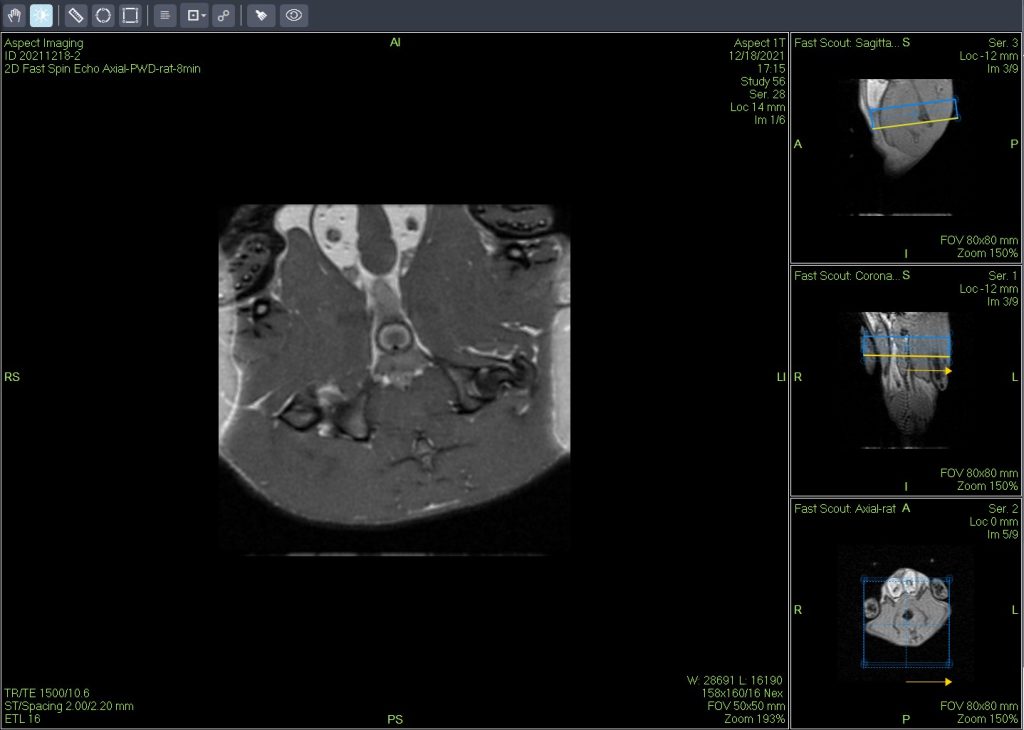

一个新的紧凑型高性能小动物磁共振成像平台(M3),该系统使用一种新的磁铁设计和一套相关的软件,降低了小动物磁共振成像仪的成本和复杂性。

Dixon脂肪抑制技术是由Dixon 提出,其基本原理是利用水、脂肪的化学位移差异,使用不同的回波时问,分别采集水和脂肪质子的in Phase 和 opposed -phase两种回波信号。

使用仪器: 小动物核磁共振成像仪NM21-040H-I 小动物核磁共振成像仪NM20-060H-I 小动物核磁共振成像仪NM42-040H-I